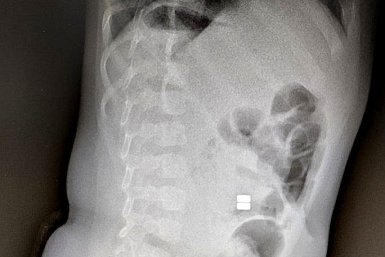

Проглоченные магнитные шарики - серьезная проблема, которая требует немедленного хирургического вмешательства министерство здравоохранения Амурской области Амурские хирурги спасают детей от смертельных шариков Число госпитализаций из-за проглоченных инородных тел растет в Приамурье 25 февраля, 15:23